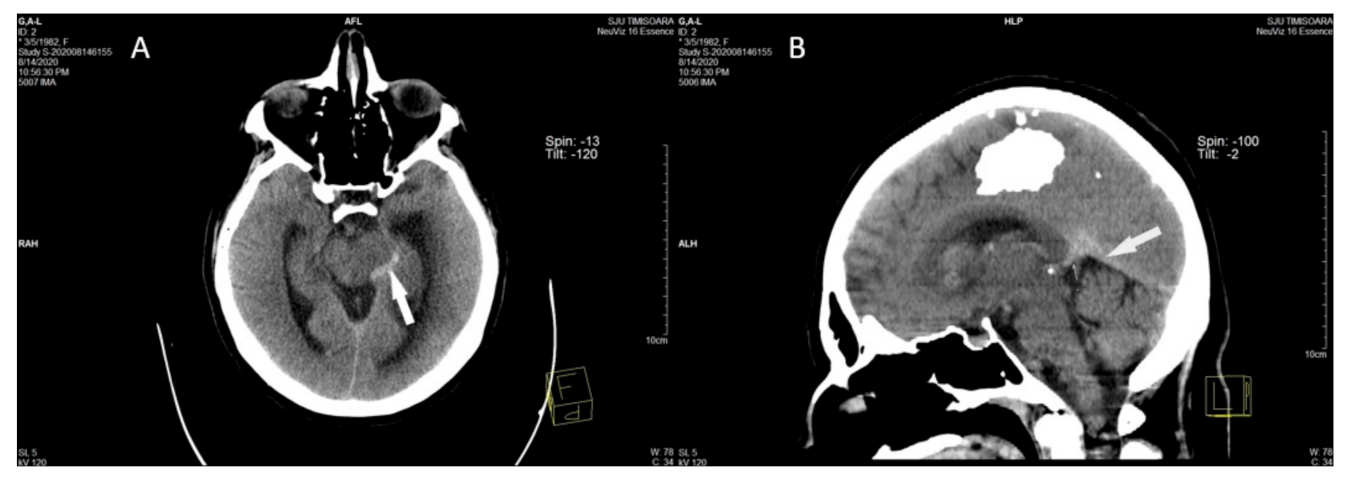

2.2. Imaging